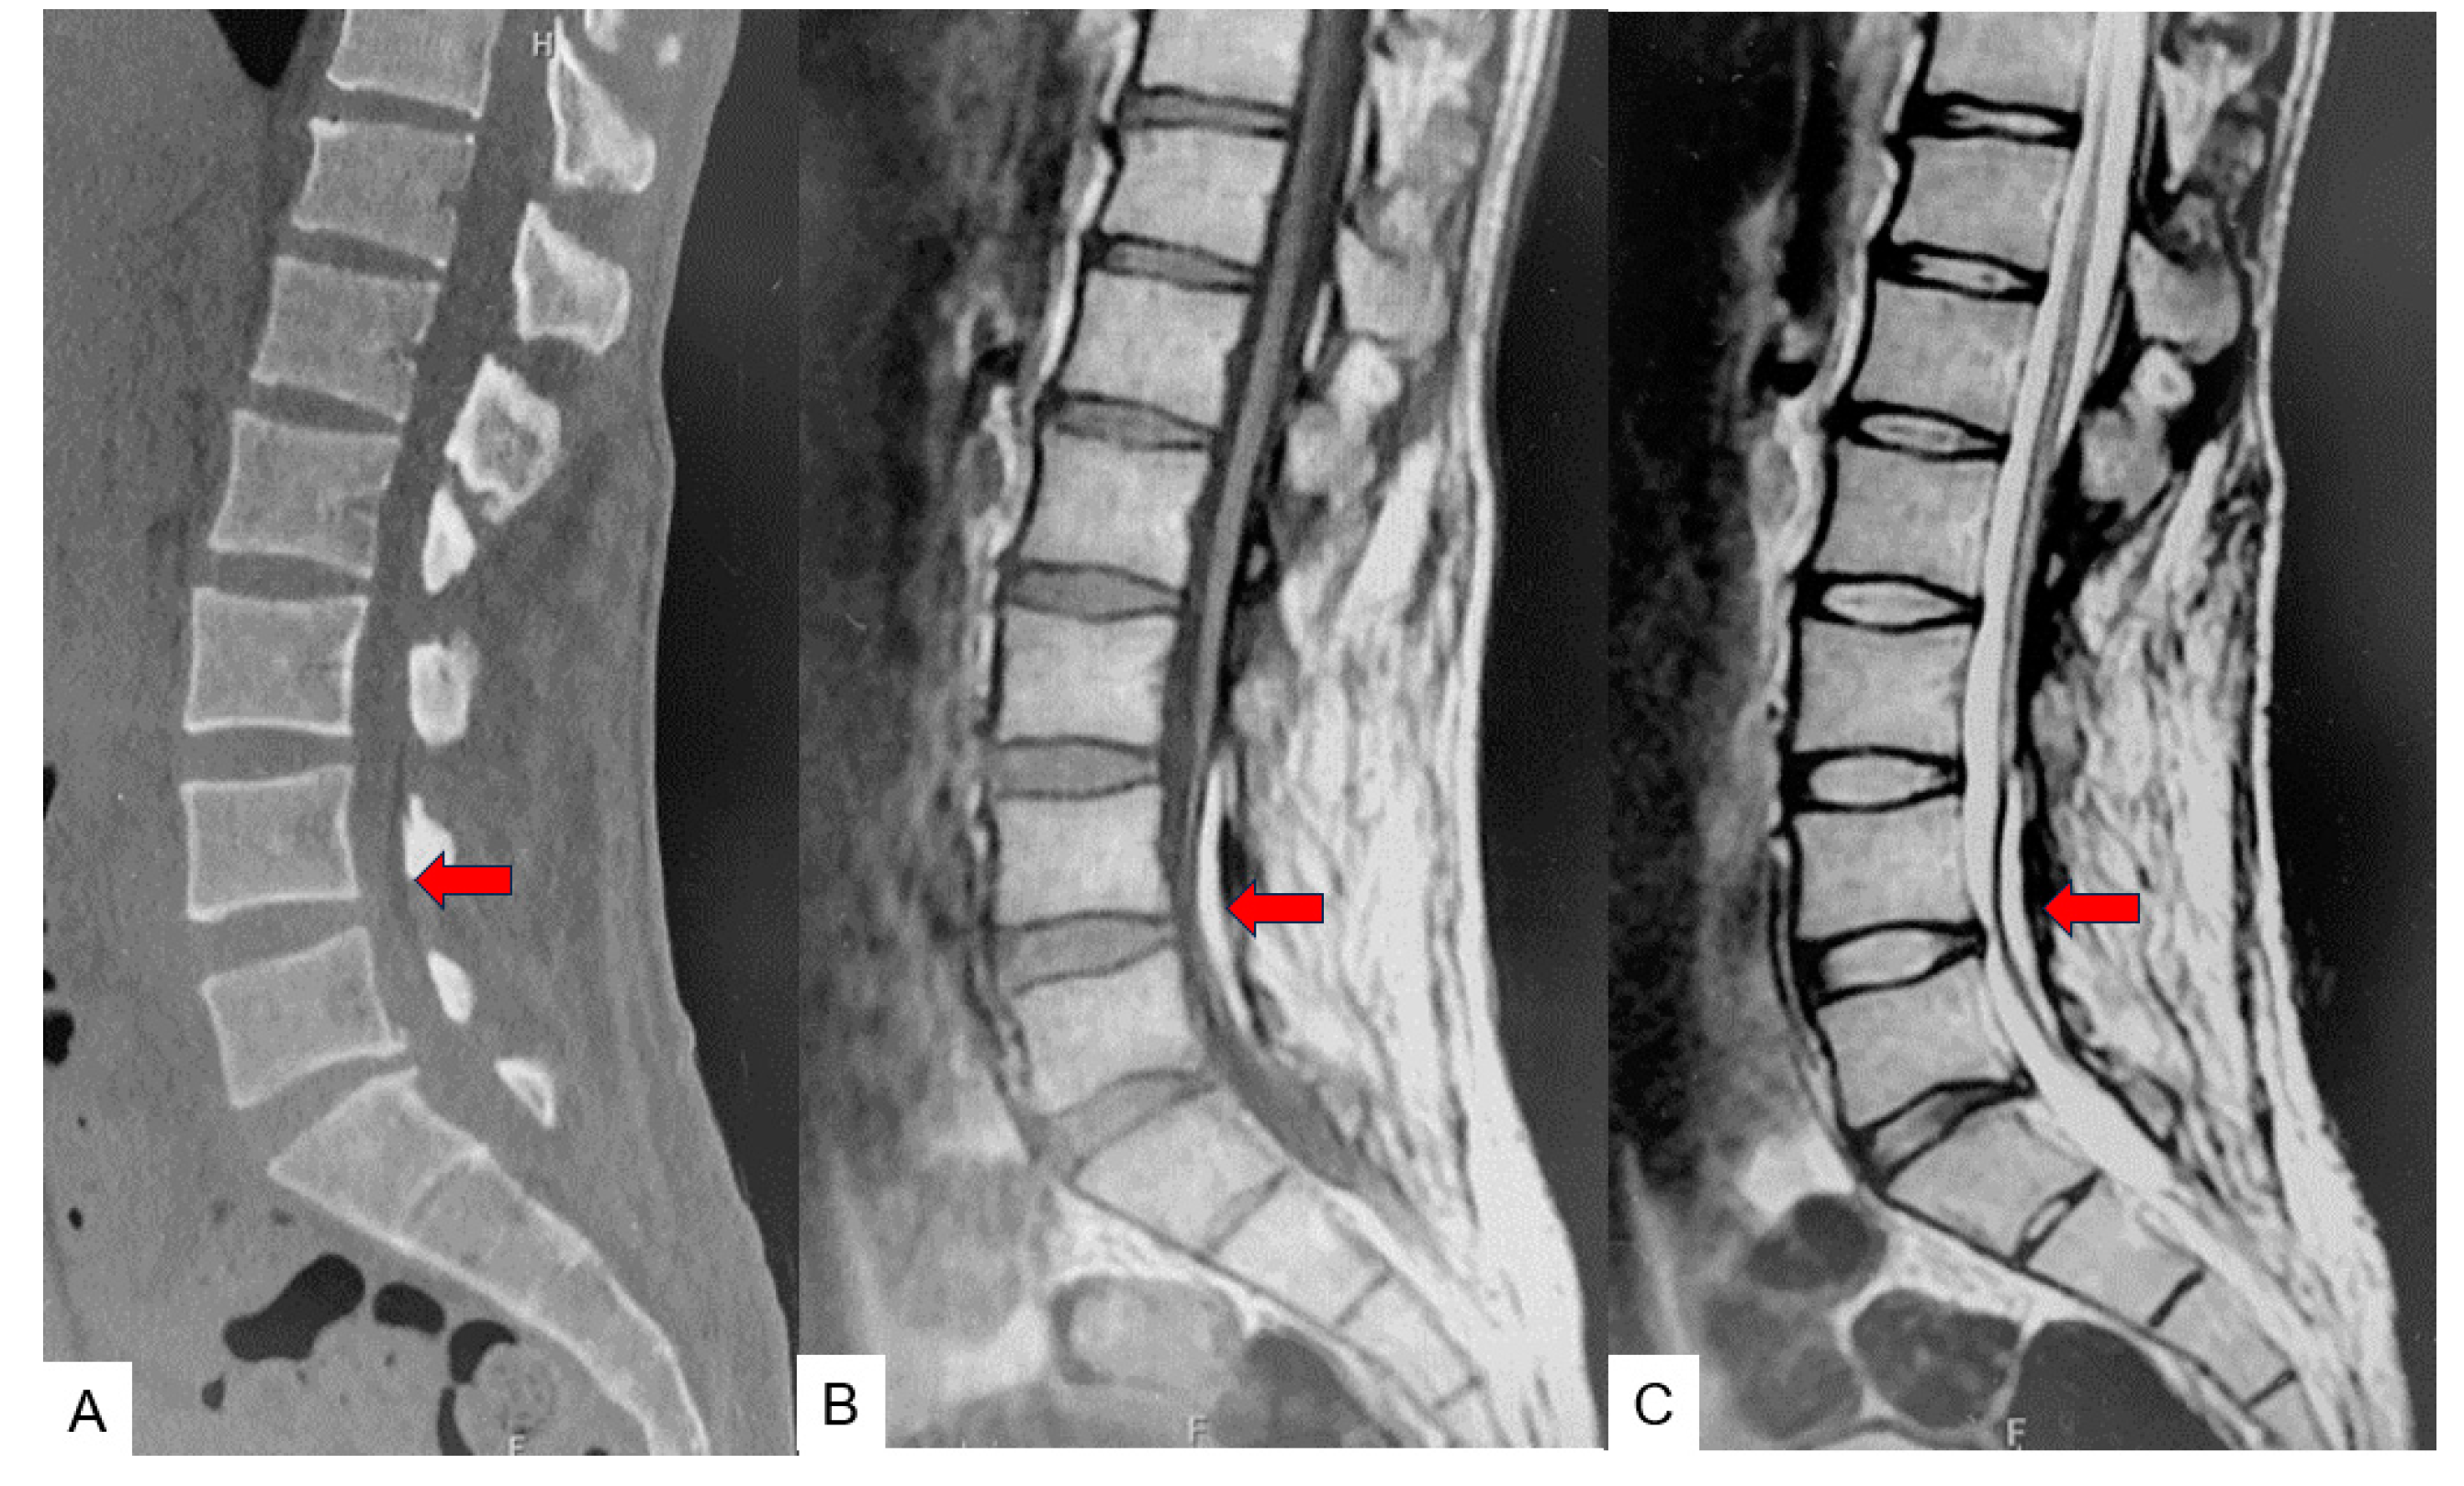

2.3. Preoperative Imaging

2.4. Surgery